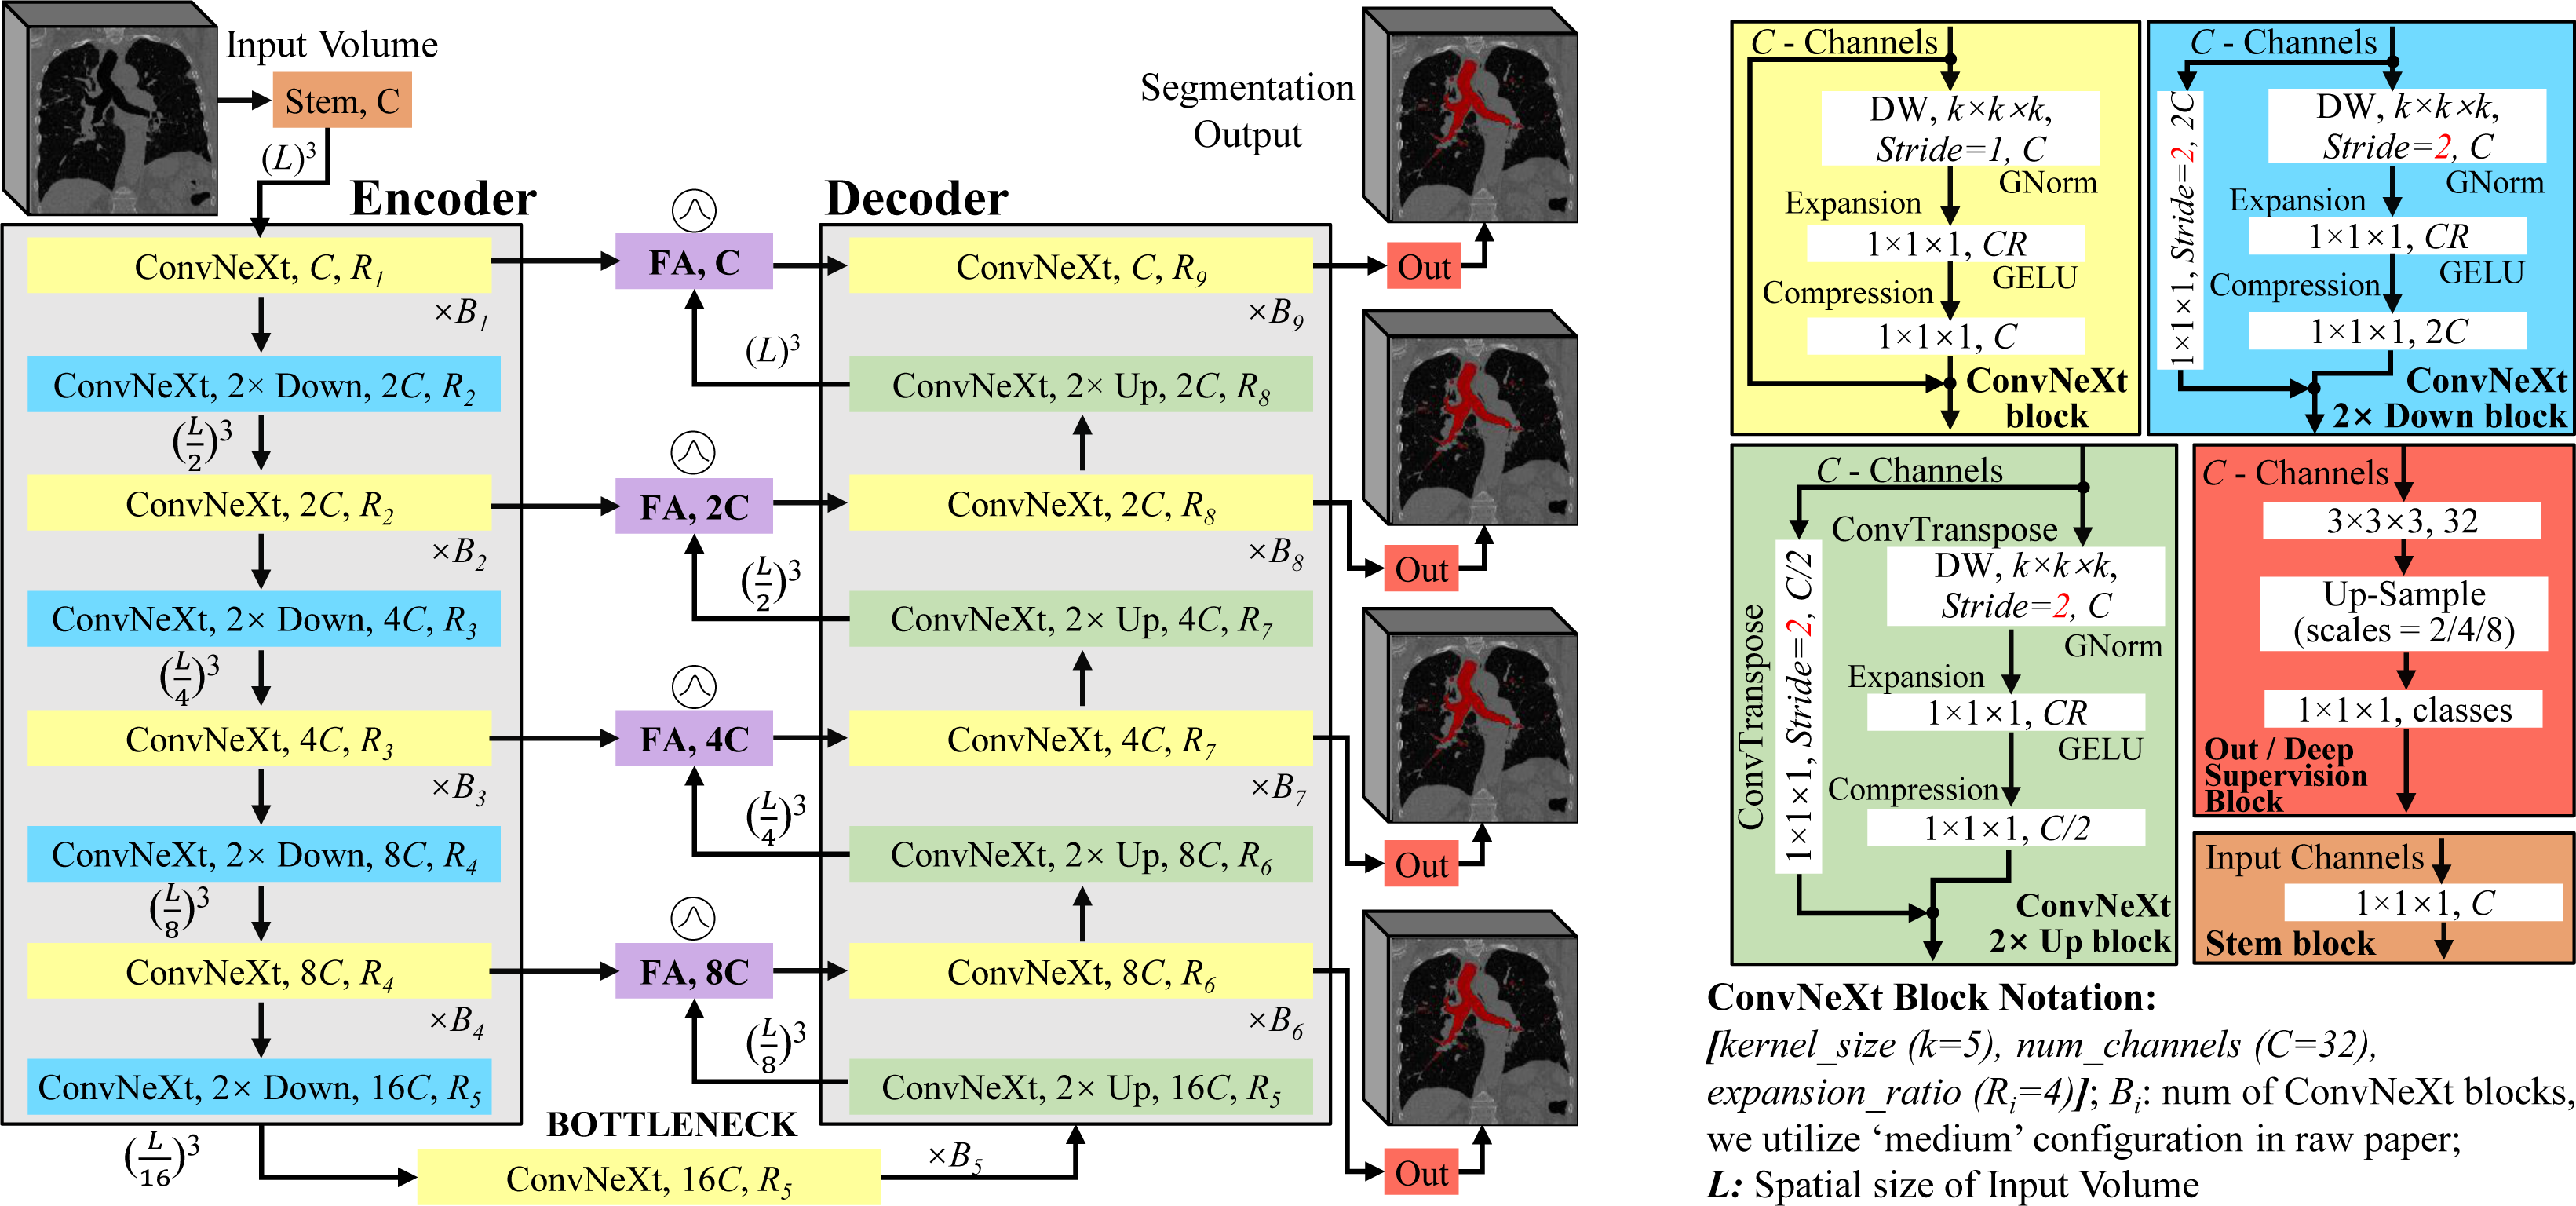

The overview of our method FABR is detailed in Fig. 2. It mainly includes two modules, i.e., fuzzy attention-based transformer-like 3D U-shaped backbone and Global-Local Cube-tree Fusion (GLCF) module. The fuzzy attention-based transformer-like backbone is inspired by the well-known ConvNeXt [20] and detailed in Fig. 3, which includes a preliminary stem, sequential transformer-like regular/down/up-sample convolution blocks, a bottleneck and four efficient fuzzy attention modules, where each convolution block is constructed by applying a large kernel of 3D separable depth-wise convolution/deconvolution, group-normalization, transformer-like architecture (i.e., embedding 4 expansion/compression convolution layers like FFN module of transformer in our Fuzzy attention module) and GELU activation layer. The corresponding layers of the same scale between the encoder and decoder are linked by the efficient fuzzy attention layer. Besides, each-scale stage of the decoder is added by the 3D convolution and activation layers to predict the preliminary coarse masks of lung organ segmentation. Then, unlike the prior top-tier methods that operate on all regular dense points of the coarse masks to render the raw prediction, the proposed GLCF module decouples and depicts the medical image regions as cube-trees, which only focuses on the recycle-sampled BVP, and renders the severe discontinuity as well as false-negative/positive bronchioles or arterioles. We now elaborate the insights within the proposed method FABR for each innovative module in the following subsections.

2.1 Fuzzy Attention-based Transformer-like Backbone

One of the key challenges to design a robust lung organ segmentation module lies in the inherent uncertainty from the organ annotations and voxel values, e.g., bronchioles and arterioles. Various efforts have been done to enhance the network to focus on pertinent regions. Notably, Attention U-Net [12] introduces an attention gate to bolster accuracy by suppressing feature activations in irrelevant regions. However, we deem that the non-channel specifics of current attention map assign the same “attention” coefficient to all feature points along the channel dimension. Specifically, given a feature map , the extant attention map is built as , while all features along the channel wise C share the same “importance”. This mechanism is unreliable since the features in different channels are extracted by different convolution kernels; therefore, we advocate the attention map to be channel-specific.

Meanwhile, numerous studies have proved the efficacy of both fuzzy logic and neural networks in data representation [10]. Broadly speaking, neural networks strive to diminish noise in original data to extract meaningful feature representations, while fuzzy logic can derive fuzzy representations, mitigating the original data uncertainty. Hence, we fuse fuzzy logic with attention mechanism by utilizing trainable Gaussian membership functions (GMFs). This fusion serves to enhance the segmentation network’s ability to focus on pertinent regions, concurrently diminishing uncertainty and variations in data representations.

As shown in Fig. 4(a), the proposed efficient fuzzy attention module is adopted within the skip connection, taking both feature maps {, } from the l-th encoder and decoder layers as inputs, which are directly yielded by the transformer-like 4 expansion/compression layers in ConvNeXt [20] backbone, followed by an instance normalization and a Leaky-ReLU layers for feature reconstitution. Then, two very lightweight squeeze-excitation (SE) layers [5] are employed to further boost the channel-specificity. Next, a voxel-wise adding operation is adopted to fuse the information, followed by a Leaky-ReLU. Eventually, the feature representations are fed into the FAG to generate a voxel-wise attention map, shown in Fig. 4(b). Assume (regardless of batch size) as the input of FAG. Due to the smoothness and concise notation of GMFs, learnable GMFs are proposed to specify the deep fuzzy sets. Each feature map (with size ) is filtered by GMFs with the trainable centre and spread